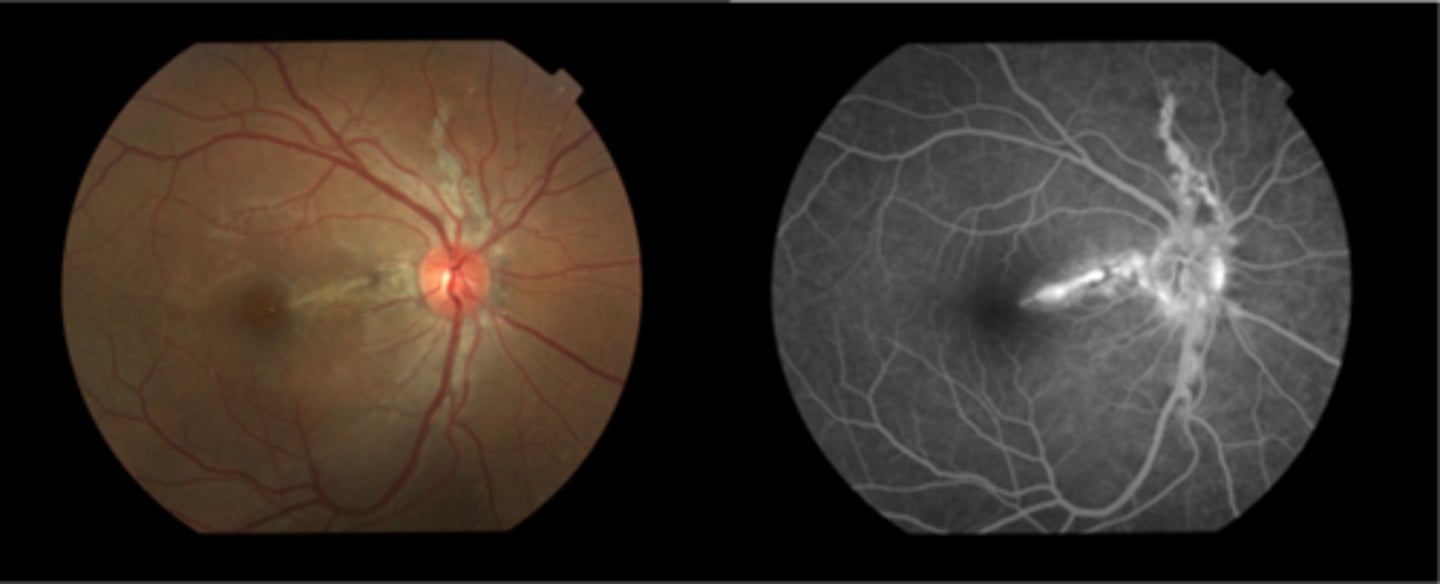

What are angioid streaks and what type of atrophy do they lead to?

breaks in Bruch's membrane in a radiating fashion emanating from the ONH = leads to RPE, PR's, choriocapillaris atrophy

What causes angioid streaks?

weakened, calcified Bruch's membrane, often in connective tissue disease = bilateral

What are the 5 CT diseases associated with angioid streaks?

PEPSI:

Pseudoxanthoma elasticum

Ehlers-Danlos syndrome

Paget's disease (of bone)

Sickle cell disease (and other hemoglobinopathies)

Idiopathic

THINK: Angie likes to drink PEPSI

How do angioid streaks affect VA?

often asymptomatic as does not involve macula

What are 2 possible complications of angioid streaks?

CNV

choroidal rupture

How do we manage angioid streaks?

educate on potential CNV or choroidal rupture, esp with injury = polycarbonate, reduced contact sports

Amsler for home monitoring

refer for CT disease workup if not already diagnosed

How does angioid streaks appear on IVFA?

hyperF bc loss of RPE = can see choroid better

How does angioid streaks appear on FAF?

hypoAF bc RPE loss/damage

What ONH finding is sometimes seen with angioid streaks?

disc drusen